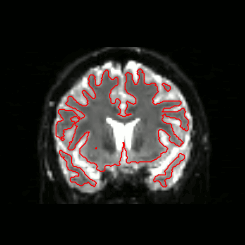

07 Masking

DWI

Quality Assessment

- One task - one QA

- General summary

- Global information

- Visual output

- Easy interface web-based